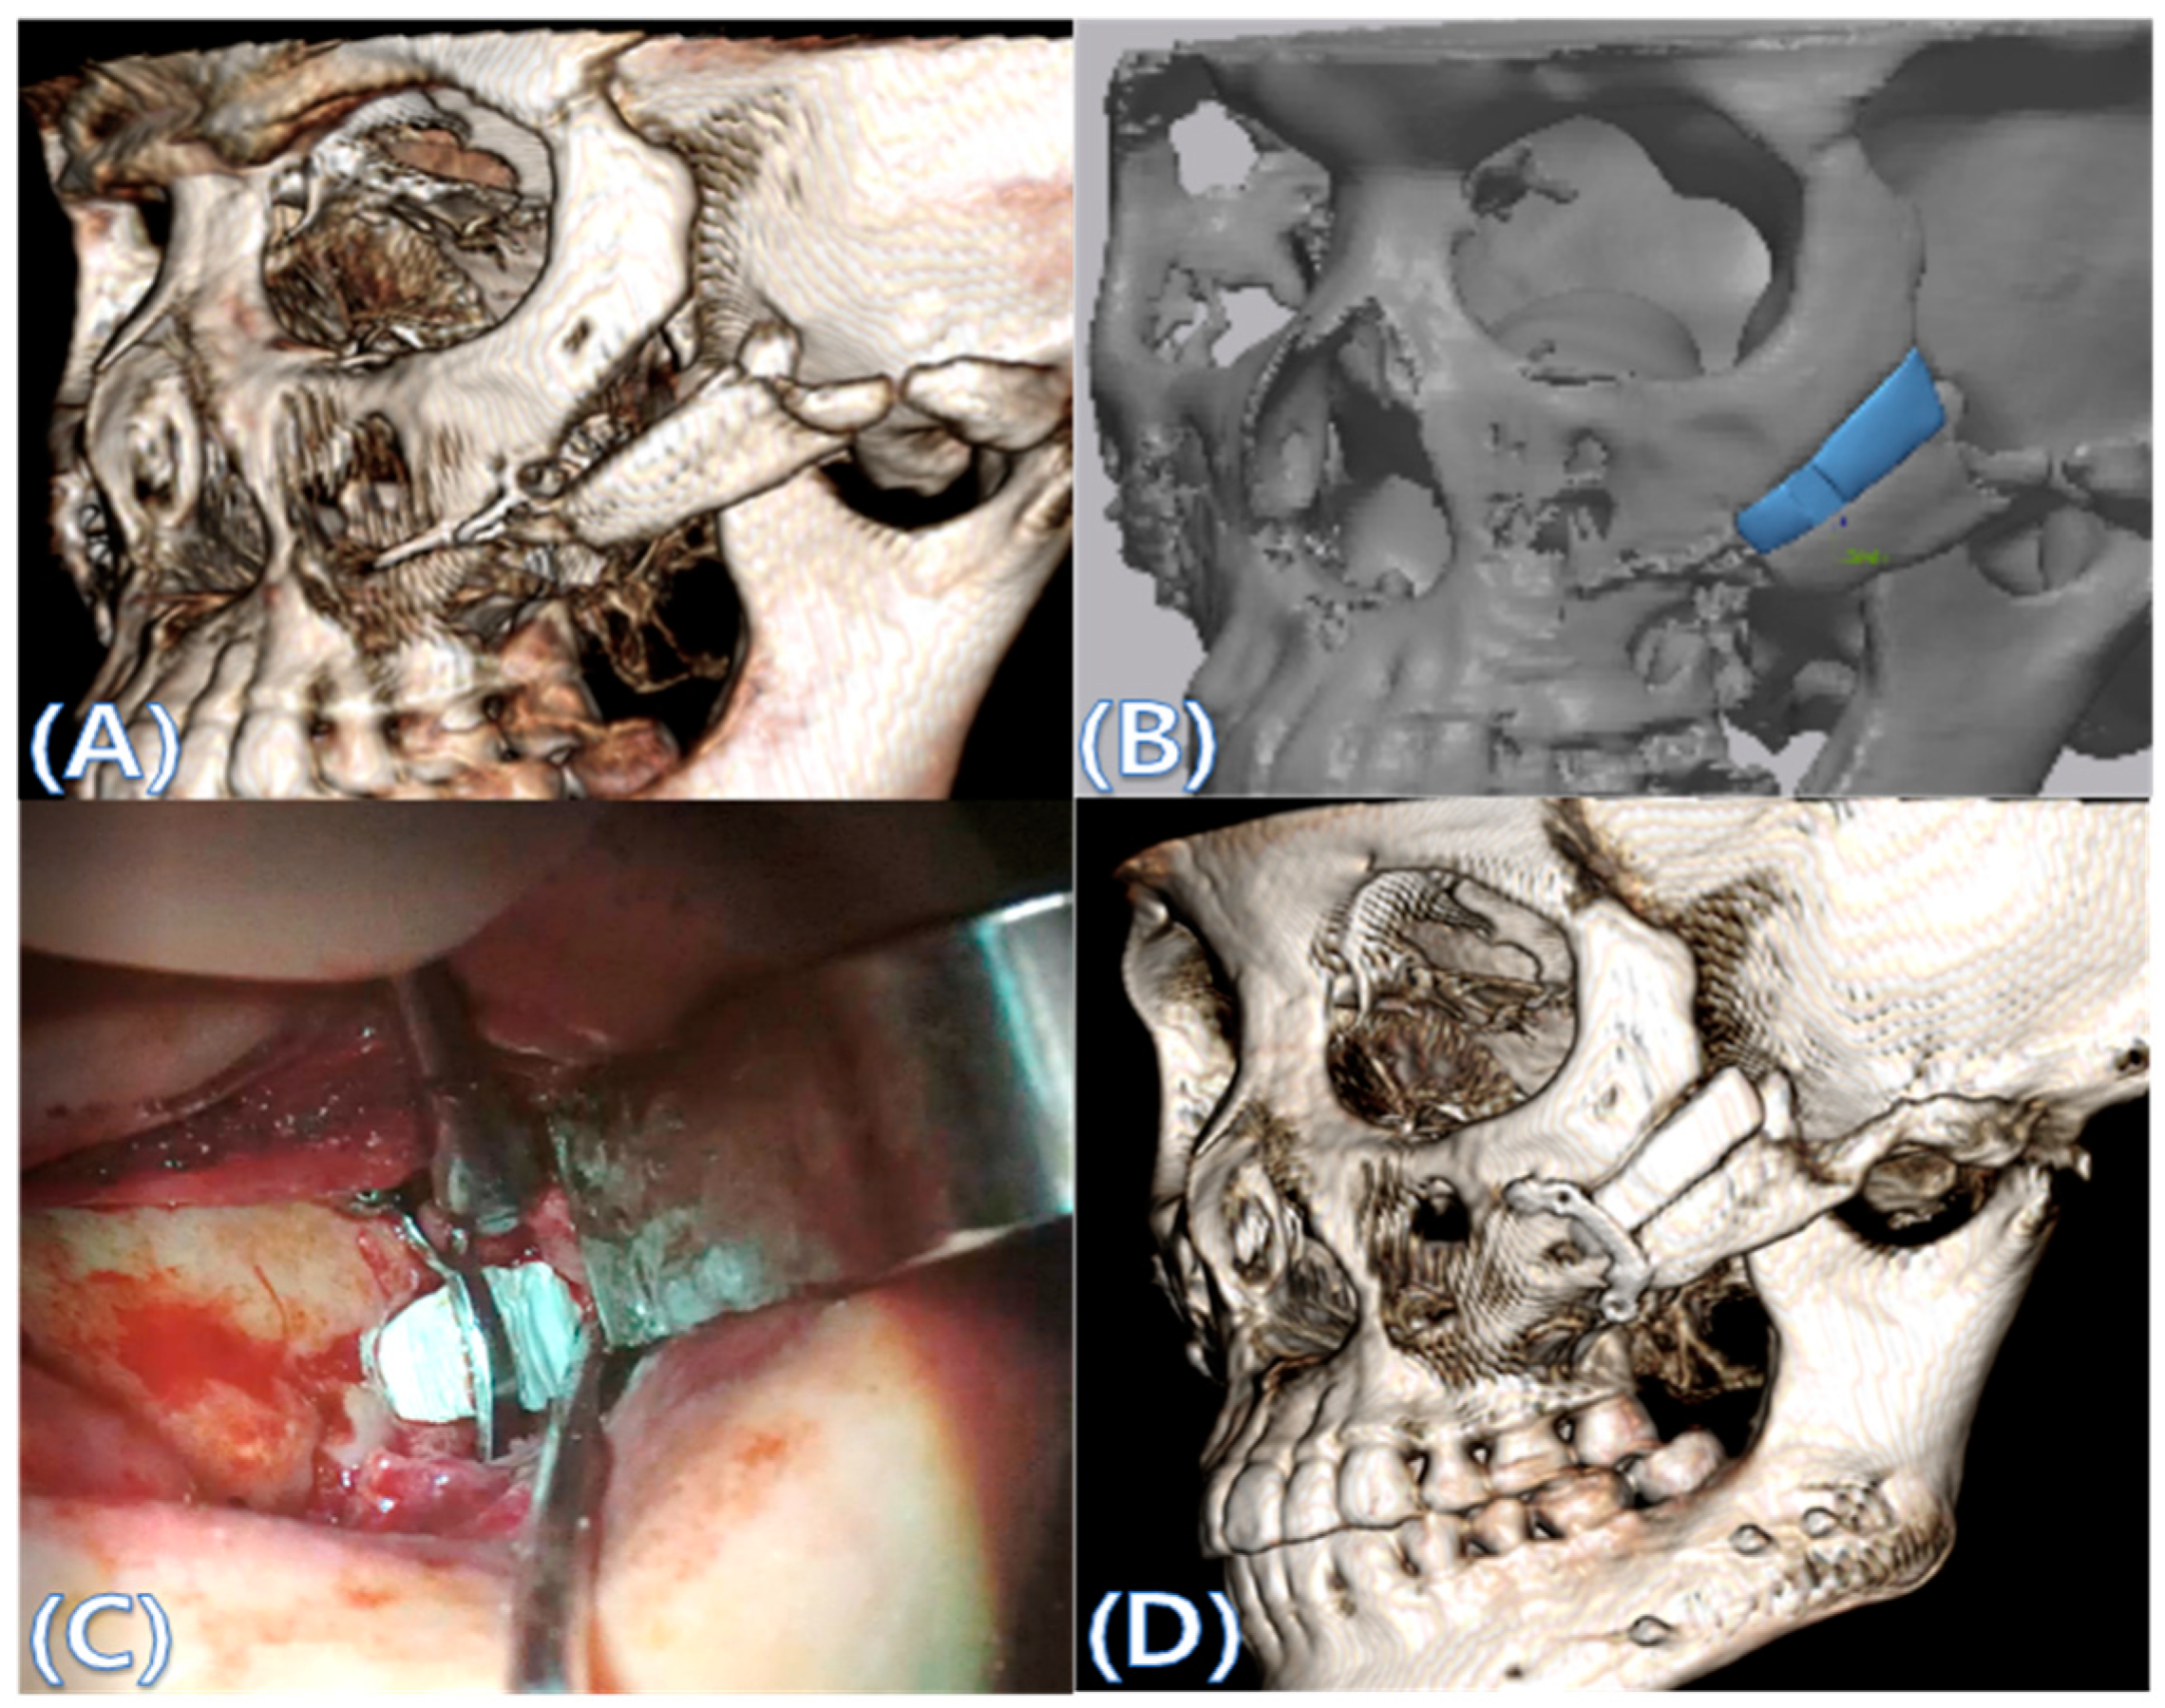

2.2. Computer-Aided Virtual Surgery, Design, and Fabrication of Patient-Specific Devices

2.3. Surgical Procedure